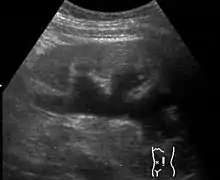

| Renal ultrasonography of hydronephrosis caused by a left ureteral stone. | |

Imaging studies, such as an intravenous urogram (IVU), renal ultrasonography, CT, or MRI, are also important investigations in determining the presence and/ or cause of hydronephrosis. Whilst ultrasound allows for visualisation of the ureters and kidneys (and determine the presence of hydronephrosis and / or hydroureter), an IVU is useful for assessing the anatomical location of the obstruction. Antegrade or retrograde pyelography will show similar findings to an IVU but offer a therapeutic option as well. Real-time ultrasounds and Doppler ultrasound tests in association with vascular resistance testing helps determine how a given obstruction is effecting urinary functionality in hydronephrotic patients.[10]